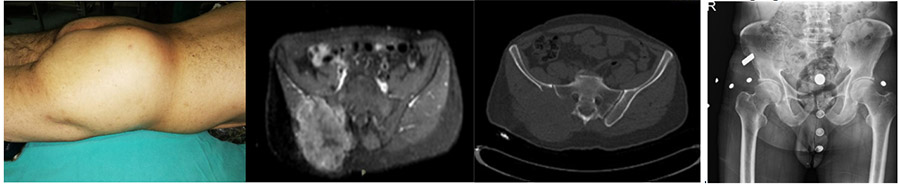

CASE 11: Lung cancer metastasis to the pelvic bone (iliac wing).

Before the surgery: Clinically, swelling is observed, X-rays show lysis, and MRI and CT scans reveal the presence of metastases, predominantly in the posterior pelvis, causing significant destruction, affecting the sacrum, and accompanied by a large tumor tissue.